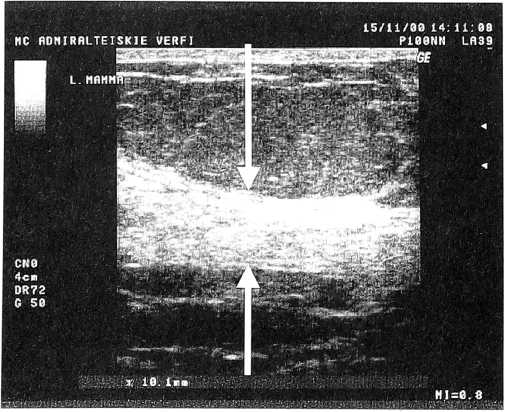

Рис. 1.

Эхограмма молочной железы пациентки 41 года, имеющей жалобы на боли в области молочных желез за 7 дней до наступления месячных. 8-й день менструального цикла. Увеличение толщины фиброгландуллярной зоны до 18 мм (крупные стрелки). Средняя эхогенность железистой ткани. Расширение млечных протоков до 2,2 мм (маленькие стрелки)

Для правильной оценки структуры молочной железы, а также степени выраженности дисгормональных диффузных процессов проводить исследование целесообразно в первую фазу менструального цикла. В целях объективной диагностики диффузной мастопатии рекомендуется измерять толщину паренхимы (фиброгландулярной ткани), что позволяет количественно дифференцировать возрастную норму и проявления диффузной мастопатии, степень выраженности диффузных процессов и изменения структуры молочных желез при динамическом наблюдении [8, 12].

Увеличение толщины паренхимы, средняя эхогенность железистой ткани, отсутствие или слабая выраженность явлений жировой инволюции, расширение протоков характерны для железистого варианта мастопатии (рис. 1); значительное повышение эхогенности железистой ткани с увеличением толщины паренхимы — для фиброзного (рис. 2); наличие множественных кист различного диаметра — для кистозного (рис. 3). Сочетание различных симптомов мастопатии характерно для ее смешанного варианта.